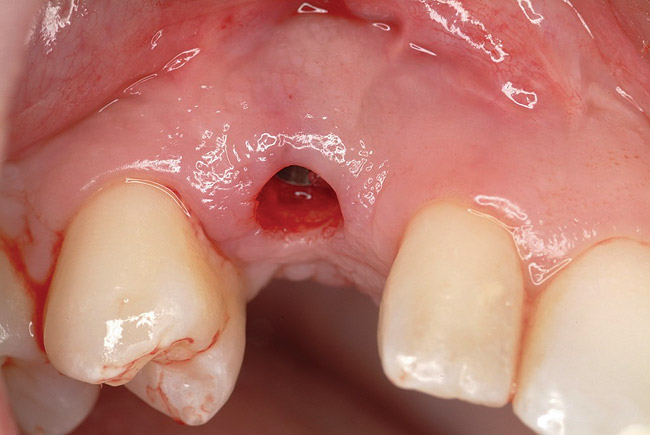

Approximately 4 months after grafting, the patient returned for clinical and 3-D radiographic evaluation. The thinnest area of ridge width preoperatively was remeasured in approximately the same location, demonstrating a gain of about 4 mm (Figure 7). The treatment plan was to place a 3.5-mm x 13-mm implant with a computer-generated guide (SiCat, Sirona Dental, www.sironausa.com), eliminating an additional open surgical procedure. Planning included initial osteotomy preparation with single-use drills combined with a localized ridge expansion using narrow, tapered osteotomes. This was performed approximately 5 months after the augmentation procedure, achieving primary stability of the implant, facilitating a transmucosal healing approach (Figure 8 and Figure 9). Following each step of osteotomy preparation, a probe was inserted along the walls of the site to confirm the integrity of the buccal and palatal walls prior to implant insertion.

Figure 8  Primary stability of the implant achieved, facilitating a transmucosal healing approach.

Figure 8

Figure 9  Primary stability of the implant achieved, facilitating a transmucosal healing approach.

Figure 9